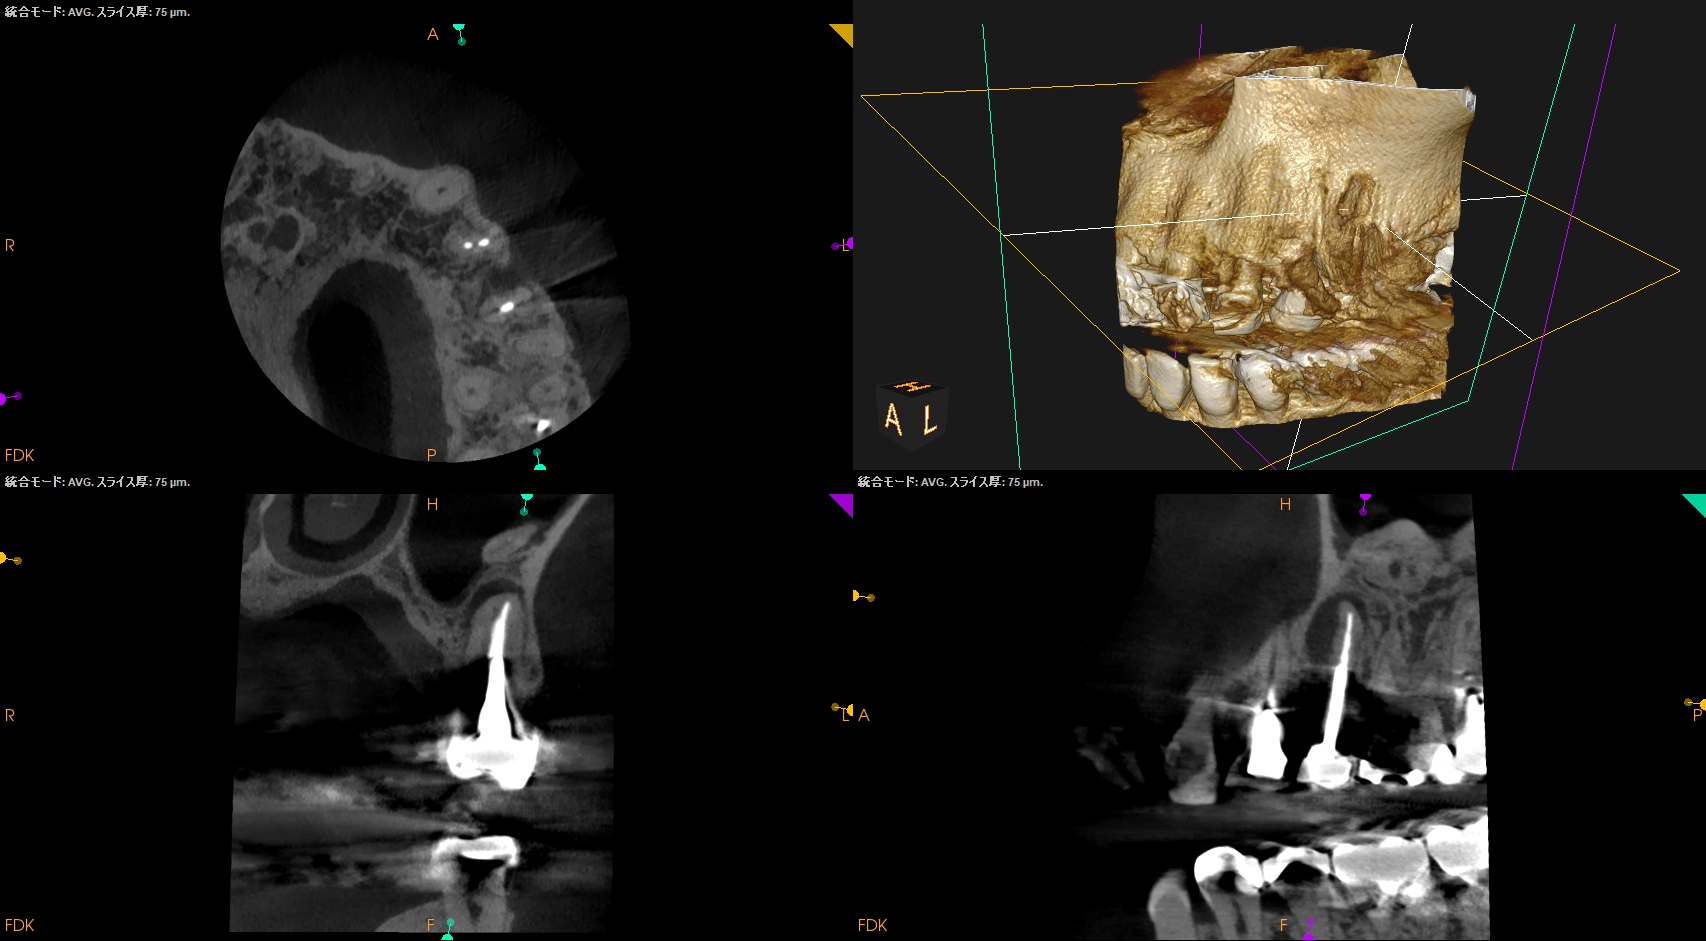

CBCT(2025.8.25)

#12 B

#12 P

#13